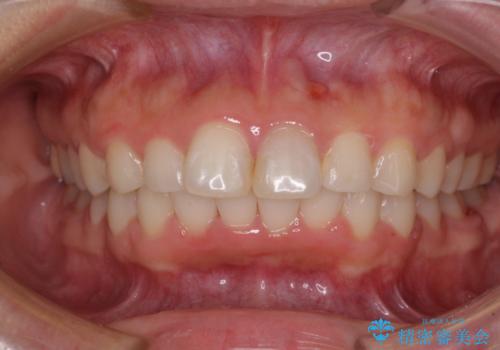

- 前に出ている上顎前歯が気になるとのことで来院された患者様です。

インビザラインを用い、IPR(歯と歯の間を削る)と歯列全体を後方に移動させることで、可能な限り前歯の突出感を改善することとしました。

元々の歯列も整っており、横顔の印象の出っ歯ではなかったため、仕上がりに満足できない可能性があると心配しておりましたが、口が閉じやすくなり、患者様には大変満足していただきました。